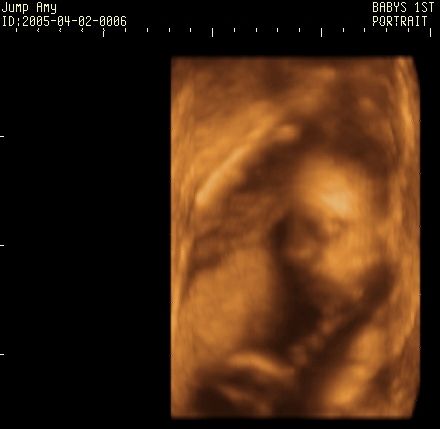

Here are some of Jack's pics.

Here are a few of the pics of Caden......I don't have the ones of Conner on this computer.